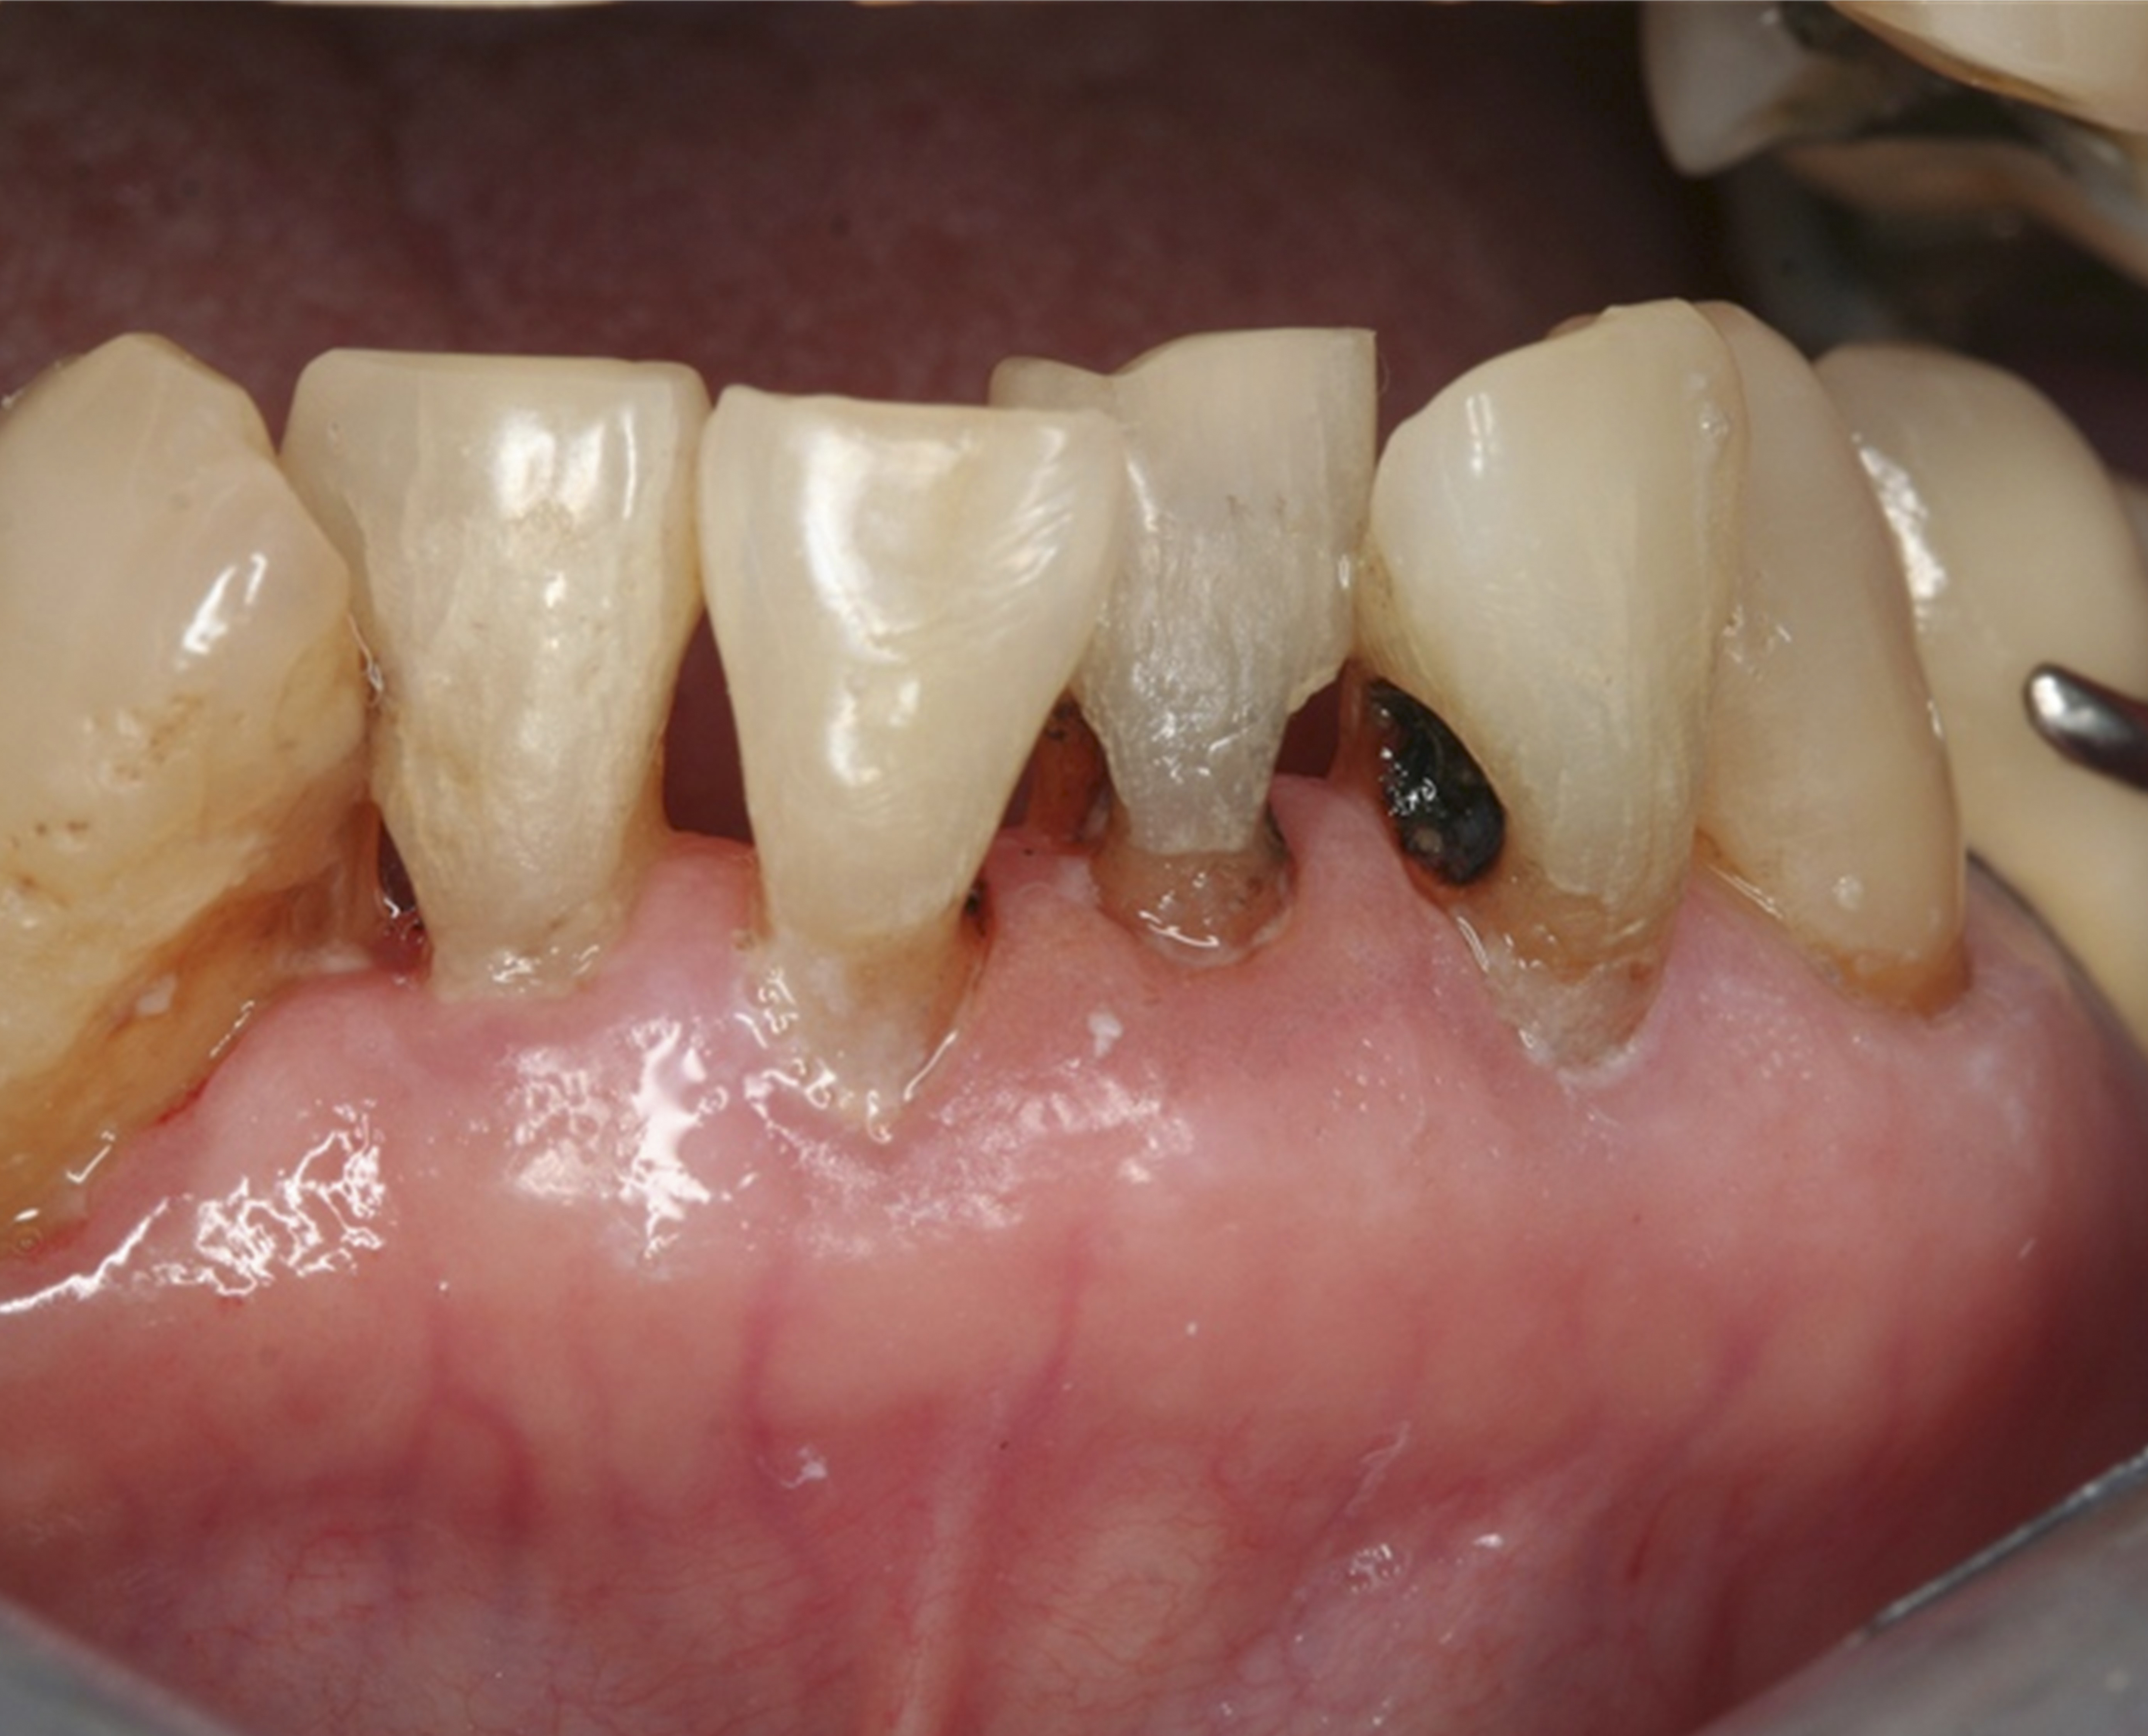

Fig 8. Use of 38% SDF to arrest rampant caries in a young teenager. Fig 8: Pre-treatment intraoral frontal view of rampant caries. Fig 9: Frontal view of arrested caries after consecutive application of SDF for 3 weeks. (images from Chu, et al, 201436 [reprinted with approval])

Figure 8

Fig 9. Use of 38% SDF to arrest rampant caries in a young teenager. Fig 8: Pre-treatment intraoral frontal view of rampant caries. Fig 9: Frontal view of arrested caries after consecutive application of SDF for 3 weeks. (images from Chu, et al, 201436 [reprinted with approval])

Figure 9

There is no consensus on the frequency of application, and 38% SDF has been used annually or biannually on clinical trials in children23,31,33,34 and in elderly.30,35 Yee and his co-worker found one-off application of 12% SDF was ineffective in arresting caries in children.31 The present authors applied 38% SDF weekly for 3 weeks to speed up the process of caries arrest and for treatment of rampant caries.36 One of the present authors’ case reports demonstrated that three weekly applications of 38% SDF can arrest rampant caries and relieve pain from hypersensitivity on a teenager. The SDF-treated caries were found arrested, and they turned coal black in appearance (Figure 9).

The inherent disadvantage of SDF is that the caries lesions will be stained black after SDF application. SDF stops caries progression by forming a hard, blackened, impermeable layer on the tooth surface that is resistant to caries (Figure 5 through Figure 9). The authors’ clinical observations are that the darker the color, the more likely the caries arrested. Some patients may not be pleased with the esthetics of this treatment outcome; therefore, it is important to inform the patients and parents (for child patients) about this treatment outcome. Moreover, SDF can stain clothes and the skin of the body. Though it does not cause any pain or damage, an SDF stain on skin cannot be easily washed away. It takes around 7 days for it to disappear, and the stain on clothes is permanent.22